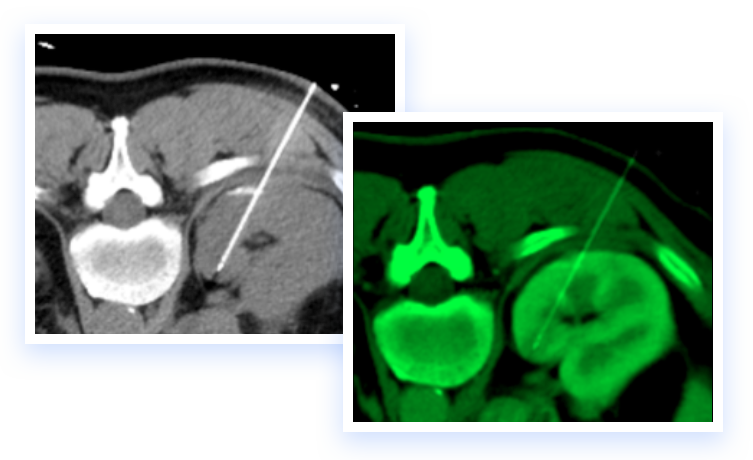

The IGTFusion System utilizes patented software algorithms to automatically align images from single and multiple image sources.

IGTFusion can visualize and register 3D image data from multiple modalities, including CT, PET, and MR images automatically.